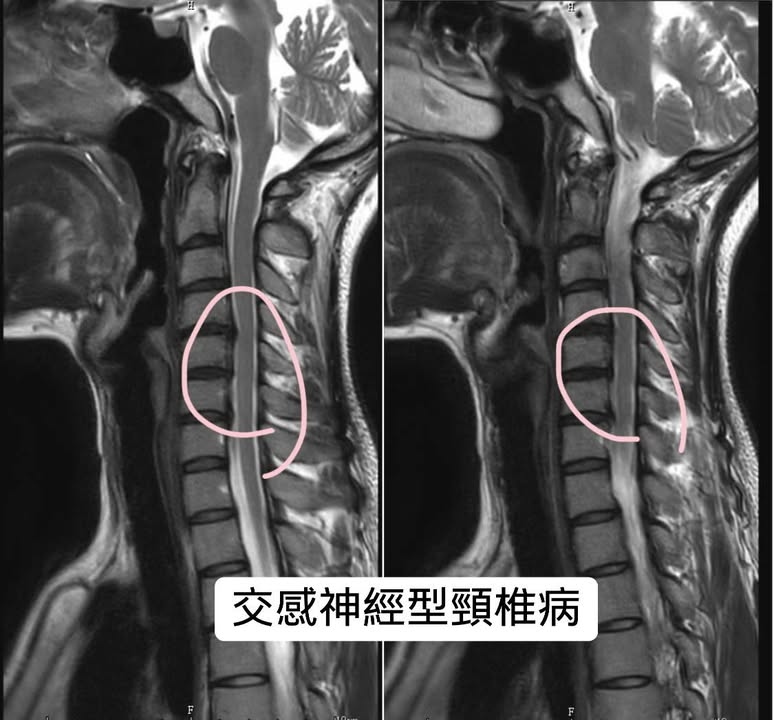

Cervical Spine Treatment Cases 頸椎治療案例 #特殊案例頸椎手術後又再度突出案例 #感謝台中劉大哥熱情見證 #親自手捏醫師娃娃公仔... 2020.11.18 #頸椎病居然會導致手快速萎縮 #脊髓型頸椎病案例 #感謝高雄王大哥熱情見證 #頸椎整合... 2020.11.13 #神經根型頸椎病讓人痛到無法入眠 #感謝新店陳小姐熱情見證 #患者的疼痛日誌讓人感動 ... 2020.11.11 #左邊膏肓長期刺痛案例原來是頸椎病 #之前一直當作肩關節問題處理沒效 #高濃度葡萄糖... 2020.11.03 #腰椎整合醫案逆轉勝 #曾經大痛到無法走路 #坐骨神經痛就是那們痛 #感謝桃園蘆竹張小... 2020.10.29 #特殊案例之味覺錯亂 #原本香甜奶油車輪餅患者覺得酸臭 #按照頸椎病治療五次後突然味... 2020.10.27 頸椎病產生的嚴重交感神經症狀 治療前後比對 2020.10.23 #等待快一年的頸椎受傷醫案追蹤 #頸椎脊髓損傷導致左邊手麻合併下肢無力患者 #前後一... 2020.10.14 #最複雜多變最痛苦難受的頸椎病 #多年的胸悶與心悸伴隨呼吸困難 #交感神經型頸椎病 #... 2020.10.13 #頸椎曲線弧度非常重要 #頸椎弧度有可能逆轉嗎 #短短三個月時間看到效果 #患者超認真... 2020.10.09 #打壘球居然腳不聽使喚跑不起來 #更恐怖的是勉強跑起來還無法剎車 #洗頭往後仰身體背... 2020.10.07 #疼痛三年頸椎病患者親手寫下治療紀錄 #交感神經型頸椎病 #症狀錯綜複雜 2020.10.02 #困擾四年多胸悶手麻頭暈醫案 #一切原因居然是頸椎出問題 #交感神經型頸椎病症狀錯綜... 2020.09.11 #交感神經型頸椎病引起的耳鳴 #耳鳴將近八個月終於得到重大改善 #曾經耳鳴到無法睡覺... 2020.08.22 #感謝板橋蘇先生熱情見證 #神經根型頸椎病卡壓 #曾痛痛到左手無法騎單車撥桿 #麻脹刺... 2020.08.04 ← 上一頁 4 5 6 7 8 下一頁 →